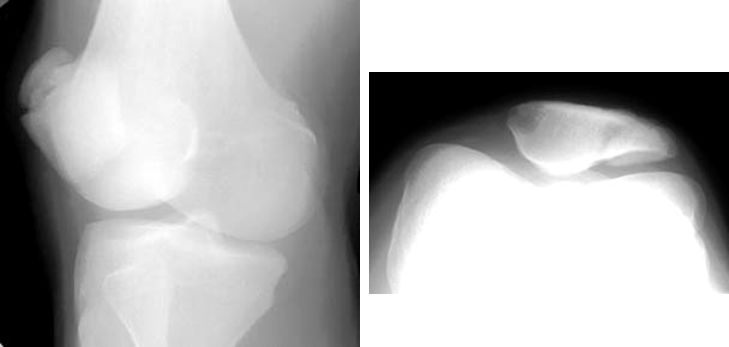

髌骨骨折

髌骨脱位